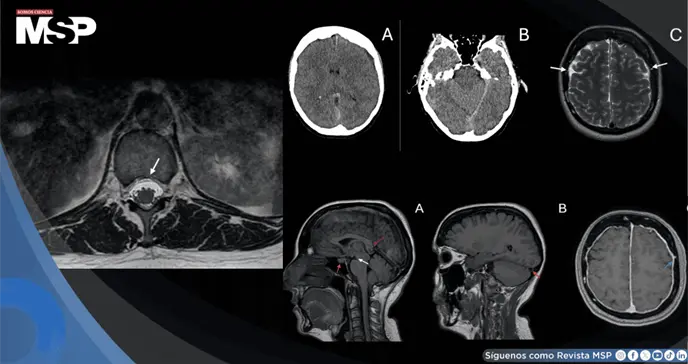

En el hospital, el examen neurológico inicial era normal. Sin embargo, al realizar una tomografía computarizada de cráneo para descartar problemas serios, los médicos encontraron un pequeño hematoma (acumulación de sangre) en el espacio que recubre el cerebro (espacio subdural).

Una resonancia magnética especializada del cerebro y de toda la columna vertebral confirmó el diagnóstico. Mostró no solo el hematoma, sino otros signos típicos de la HIE, como un engrosamiento de las membranas que cubren el cerebro y, lo más importante, una pequeña fuga de líquido cefalorraquídeo en la parte baja de la columna (a la altura de las vértebras torácicas T12-L1).